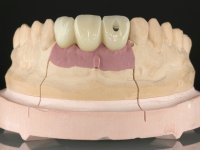

In the initial phase, it was proposed to the patient to perform the surgical implant exposure and after clinical evaluation, make prosthetic decisions. Once the healing screw was placed and the soft tissues were healed, an inadequate position of the implant was found. In view of the dramatic situation, the patient was proposed to remove the implant and put a new one after tissue regeneration. This proposal was rejected by the patient, who suggested temporary rehabilitation of the current implant. A new proposal was then made, to rehabilitate the implant, consisting of a screwed abutment, and on this, the placement of an acrylic crown with coronal and gingival components. After 6 years with the provisional treatment, the patient appeared in consultation with an abscess in tooth 1.1. After clinical and imaging analysis, it was decided to remove teeth 1.1 and 2.2, submerge the implant, place two implants at the site of 1.1 and 2.2 and perform adequate tissue regeneration. Temporization would be done with a provisional 3-element bridge, adhered with a net to the neighboring teeth. After osseointegration, definitive rehabilitation would be done with a 3-element bridge, including zirconia infrastructure and ceramic cover.

The surgical implant exposure and the healing screw placement proved to be a negative surprise regarding its position. Since the proposed removal of the implant was refused, we advanced to its provisional rehabilitation. An open tray impression technique was done, and a screwed abutment with a coronal and gingival component and an acrylic crown were made in the laboratory, using these two components. The provisional crown was placed in the mouth until a final decision was made. Six years passed before the patient returned to the clinic with an abscess on tooth 1.1. The choice to remove teeth 1.1 and 2.2 was made, to create a provisional 3-element bridge with a net to be adhered to the adjacent teeth. Surgery was planned and performed, placing the two implants at the site of 1.1 and 2.2, and the implant at the 2.1 site was cut with the objective of submerging it, while adequate tissue regeneration was performed (Surgical Work performed By Dr. Manuel Neves). During osseointegration, the patient used the fixed provisional bridge. A first impression was made for confection of a zirconia screwed provisional bridge, which worked the soft tissues for twelve weeks. The definitive impression was made with the individualisation of custom impression copings. Final rehabilitation was done with ceramized abutments, and also a bridge with zirconia infrastructure and ceramic cover. Due to the inclination of the implant placed at the site of tooth 1.1, the bridge required cemented fixation.